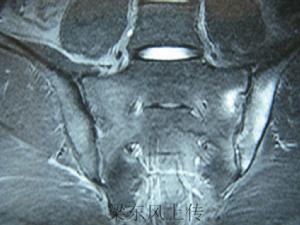

X線表現對強直性脊柱炎具有診斷意義。強直性脊柱炎最早的變化發生在骶髂關節。該處的X線片顯示軟骨下骨緣模糊,骨質糜爛,關節間隙模糊,骨密度增高及關節融合。通常按X線片骶髂關節炎的病變程度分為5級:0級為正常;Ⅰ級可疑;Ⅱ級有輕度骶髂關節炎;Ⅲ級有中度骶髂關節炎;Ⅳ級為關節融合強直。圖1顯示骶髂關節Ⅲ級病變。

對於臨床可疑病例,而X線片尚未顯示明確的或Ⅱ級以上的雙側骶髂關節炎改變者,應該採用計算機斷層(CT)檢查。該技術的優點還在於假陽性少。但是,由於骶髂關節解剖學的上部為韌帶,因其附著引起影像學上的關節間隙不規則和增寬,給判斷帶來困難。另外,類似於關節間隙狹窄和糜爛的骶髂關節髂骨部分的軟骨下老化是一自然現象,不應該視為異常。見圖2。

磁共振成像技術(MRI)對於骶髂關節炎症以及脊柱炎症的判斷價值要優於CT,只有MRI檢查能夠顯示強直性脊柱炎骶髂關節炎0級病變,MRI的優勢在於通過觀察強直性脊柱炎骶髂關節滑膜軟骨和關節面下骨的形態和信號改變,達到早期發現和診斷強直性脊柱炎的目的。見圖3.